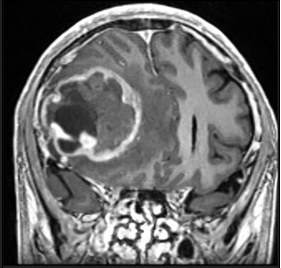

A 51-year-old male with a medical history of Neurofibromatosis type 2 presented with a clinical progression spanning 3 months, characterized by difficulties in concentration, short- term memory loss, and a frontal oppressive-type headache rated 5/10 on the analog pain scale, exacerbated by the Valsalva maneuver. Imaging studies revealed a hypodense lesion with central necrosis in the right frontal lobe accompanied by perilesional edema, resulting in interhemispheric line displacement. Additionally, there was partial collapse of the ipsilateral lateral ventricle and subfacial herniation.

Figure 1 Preoperative tomography, coronal view.

Figure 2 Preoperative tomography, axial view.